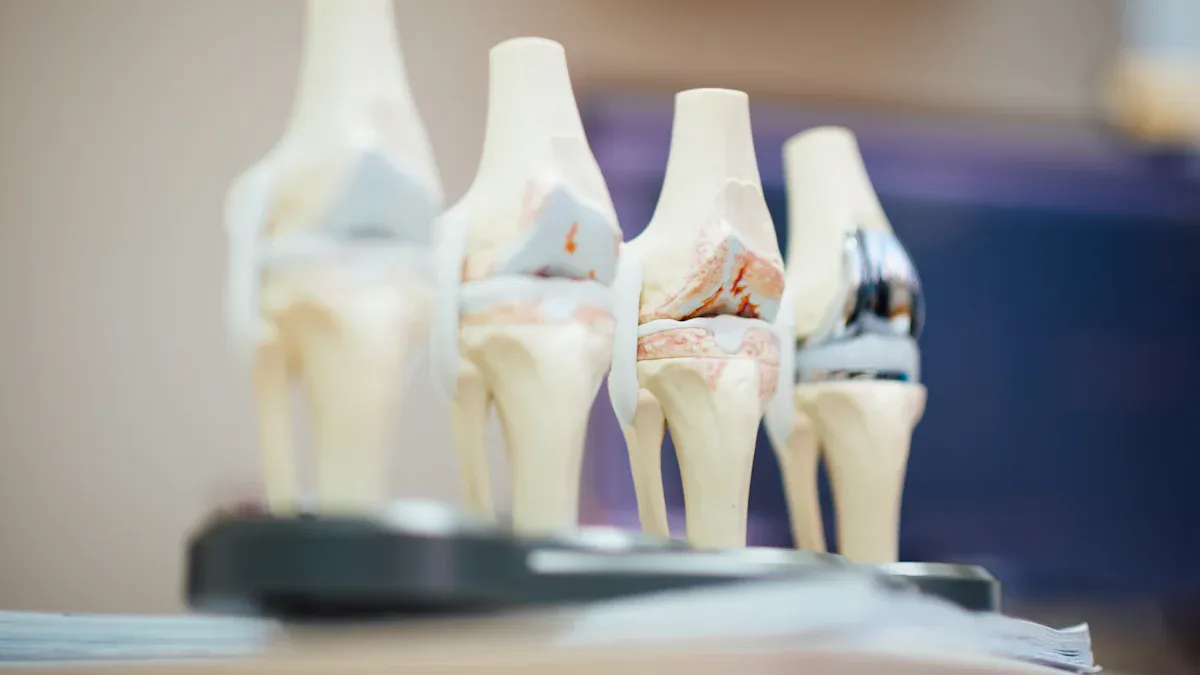

There are many kinds of spinal implants used in surgery. Doctors pick the right device for your problem and treatment plan. The main groups are fusion and non-fusion spinal implants. Each group has its own features and jobs.

Fusion spinal implants join two or more vertebrae together. These devices keep your spine steady and help with pain. You might need fusion if you have degenerative disc disease, trauma, or spondylolisthesis. Some common fusion spinal implants are pedicle screws, rods, plates, and interbody cages. These devices hold bones in place while they heal and fuse.

Non-fusion spinal implants let your spine keep moving. These devices do not join bones together. They support your spine and help with pain. Non-fusion implants include artificial disc replacement and expandable rods. Doctors use non-fusion implants when you need to keep your spine flexible.

Many devices are used in spinal surgery. Each device helps support or fix your spine.

Plates: Plates connect bones and keep them steady during fusion.

Rods: Rods hold vertebrae together and help fix spine shape.

Interbody cages: Cages go between vertebrae and help fusion.

Artificial discs: Artificial discs replace damaged discs and keep your spine moving.

Screws: Screws attach plates and rods to bones.